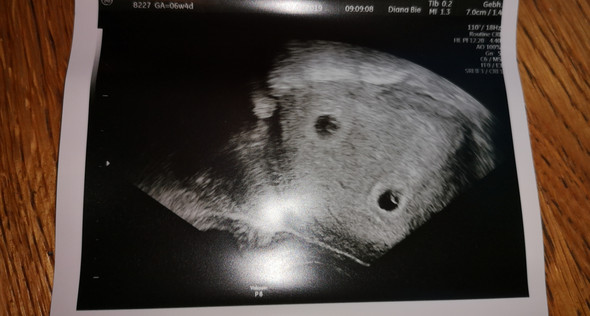

Und am Ende heißt es wieder, siehst du, ich hab es gewusst. Der starke Glaube an eine Schwangerschaft kann sogar die Menstruation später als üblich einsetzen lassen. So kamen dann in unserem Kleiderschrank 4 kleine Würmchen mit Drama auf die Welt,die Mama war überfordert und wir mussten alle abnabeln teilweise saubermachen und den Kreislauf anregen,eins atmete zu Anfang nicht,wir haben abgesaugt und beatmet und hofften,das Richtige zu tun. Schwangerschaftstest mit positivem Ergebnis Ein Schwangerschaftstest kann ab dem ersten Tag der üblicherweise beginnenden Periode gemacht werden. Jenny: Inzwischen weisst Du ja, dass es nicht gut ist, wenn Deine Katze mit ihrem Bruder Junge bekommt, da da genetisch viel schieflaufen kann. Ich muss Nala recht geben, Kanichennachwuchs sollte man nicht gewollt herbeiführen.